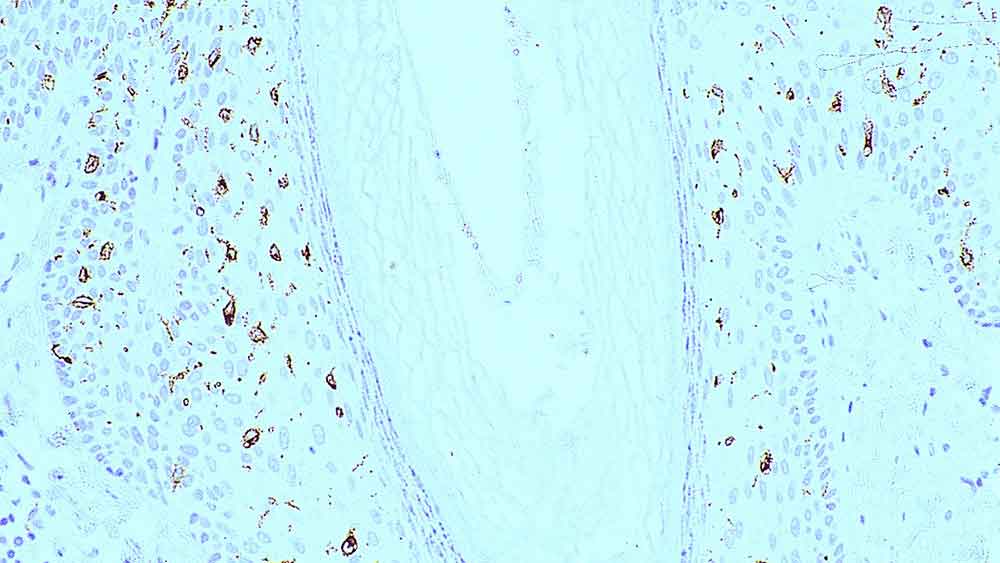

Immunohistochemical staining for Helicobacter pylori: clone ULC3R

Le clone ULC3R, contrairement aux autres anticorps polyclonaux dirigés contre l'Helicobacter pylori, ne présente pas de réaction croisée avec la Campylobacter jejuni (une bactérie gastrique qui entraîne une diarrhée infectieuse). Le clone ULC3R permet également un marquage mieux défini que celui du NCL-HPp. Le clone d'anticorps ULC3R, sera utile pour identifier et différencier les patients chez lesquels l'éradication de la bactérie s'impose, des patients qui présentent un risque plus élevé de développer des maladies cliniques liées à l'infection par H. pylori.